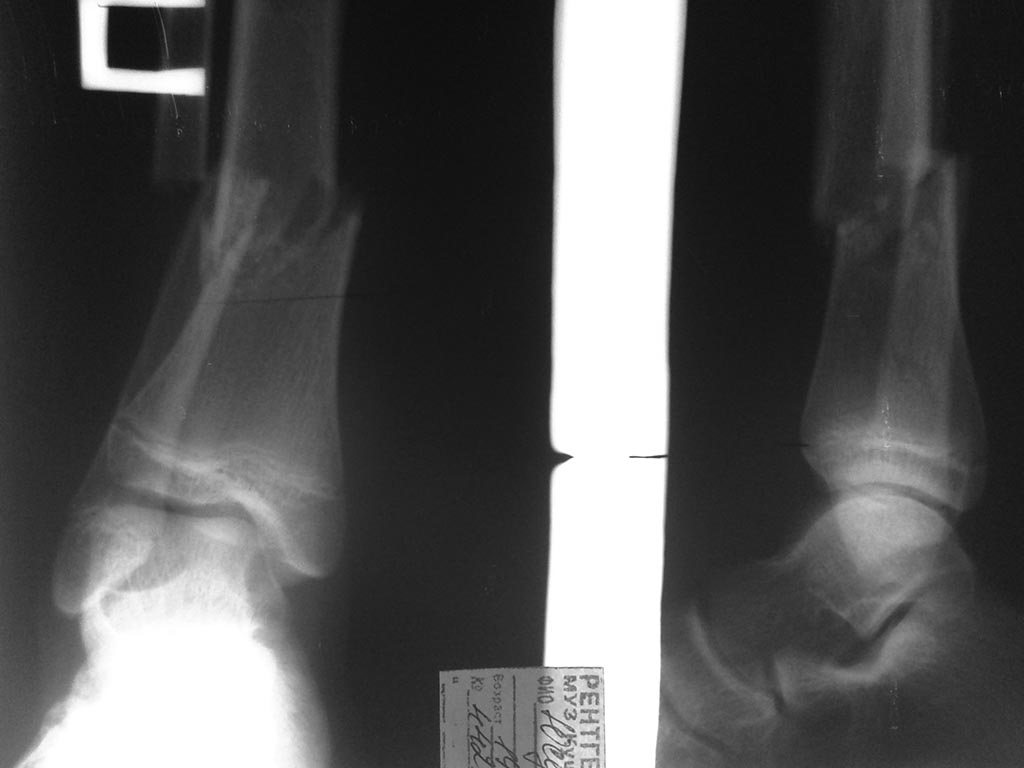

Уважаемые коллеги!Прошу разъяснить ситуацию-каким способом вы предпочитаете синтезировать подобные переломы? В нашем отделении даются рекомендации оперировать подобные переломы открыто - LCP. Аргумент против БИОС - возможная нестабильность, учитывая короткий дистальный фрагмент. С какими проблемами можно столкнуться в ходе имплантации штифта, реабилитационном периоде? Спасибо за внимание!

Если имеется ввиду только локализация перелома, на зоны роста не отвлекаемся - тут, конечно, заштифтовать вполне можно, имплантатов с возможностью ввести 4-5 винтов в короткий дистальный отломок только ленивый не выпустил еще.

Проблемы "в ходе имплантации" - надо четко представлять итоговое положение отломков, и где должен оказаться гвоздь. На круглой короткой картинке на экране рентгеновского аппарата легко вальгусное положение принять за нормальное. Надо помнить, что гвоздь должен идти параллельно латеральной стенке, и не в центр, а латеральнее. Лучше сразу ввести отклонющие спицы. У больных с хорошим качеством кости надо длинной разверткой сделать в губке канал под гвоздь, иначе можно эпифиз расколоть. Несмещенный перелом заднего края и без этого бывает, надо его до дистракции 2-3 передне-задними спицами зафиксировать временно.

А если про этот конкретный случай, с зонами роста - тут сложнее выбор, не только гвоздь vs пластина, но еще и аппарат актуален.